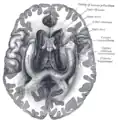

![]() Base of brain (Tuber cinerum visible at center). | |

The tuber cinereum is the portion of hypothalamus[1] forming the floor of the third ventricle situated between the optic chiasm, and the mammillary bodies.[2] The tuberal region is one of the three regions of the hypothalamus, the other two being the chiasmatic region and the mamillary region.[1]

The tuber cinereum is situated caudal to the optic chiasm, medial to the optic tract (which flanks it on either side), and rostral to the two mammillary bodies.[4] is continuous anteriorly with the lamina terminalis, and laterally with the anterior perforated substances.